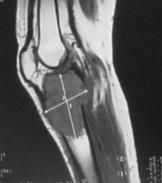

MRI (Magnetic resonance imaging / Manyetik rezonans görüntüleme)

Tümörün yumuşak doku ve kemik iliğinde yayılımını değerlendirmek için MRI kullanılır. Düz grafiden sonra yapılması gereken incelemedir. Ancak MRI bazen gereğinden fazla ayrıntı gösterebilir. Örneğin osteoid osteoma gibi bazı tümörler aşırı ödem nedeni ile kötü huylu tümörlere benzer görüntü verebildiğinden yanıltıcı olabilir.